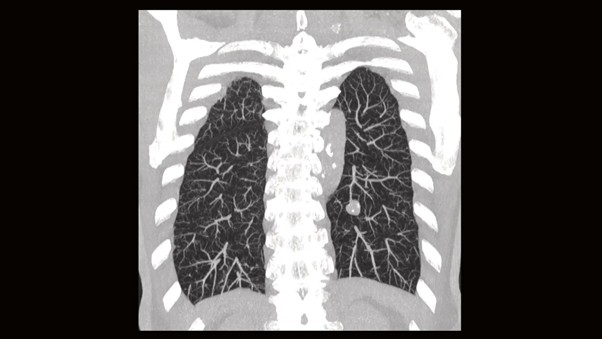

В современных аппаратах используется технология спирального сканирования. В отличие от старых пошаговых методов, где стол двигался, останавливался и после снимка двигался снова, здесь процессы происходят одновременно. Стол с пациентом плавно едет через гентри, а трубка непрерывно вращается вокруг него. Траектория луча относительно тела пациента напоминает спираль или пружину. Можно сканировать целые анатомические области, например всю грудную клетку, за один проход и всего за несколько секунд, что исключает пропуски зон между срезами.

- Визуализация и реконструкция

Изначально компьютерный томограф получает только аксиальные срезы — это поперечные «ломтики» тела, как если бы мы смотрели на пациента со стороны ног. Современные мощные станции мгновенно выполняют мультипланарную реконструкцию (MPR). Это значит, что программа берет стопку поперечных срезов и строит из них изображения в других плоскостях:

- фронтальная (корональная) — вид спереди;

- сагиттальная — вид сбоку;

- 3D-модель — объемное изображение костей и сосудов.

Таким образом, из одного сканирования врач получает полную трехмерную картину состояния пациента.

Снимок легких на КТ Siemens SOMATOM go.Now.